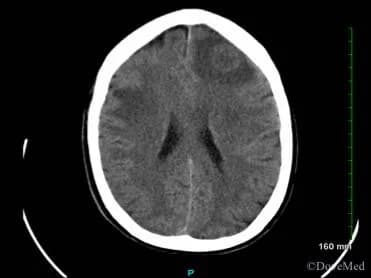

Glioblastoma is the most common primary brain tumor in adults and among the top five causes of death due to cancer. An estimated 12,120 people will be diagnosed with glioblastoma in the United States this year.1 Glioblastoma occurs primarily in older people; the average age at diagnosis is 64 years.